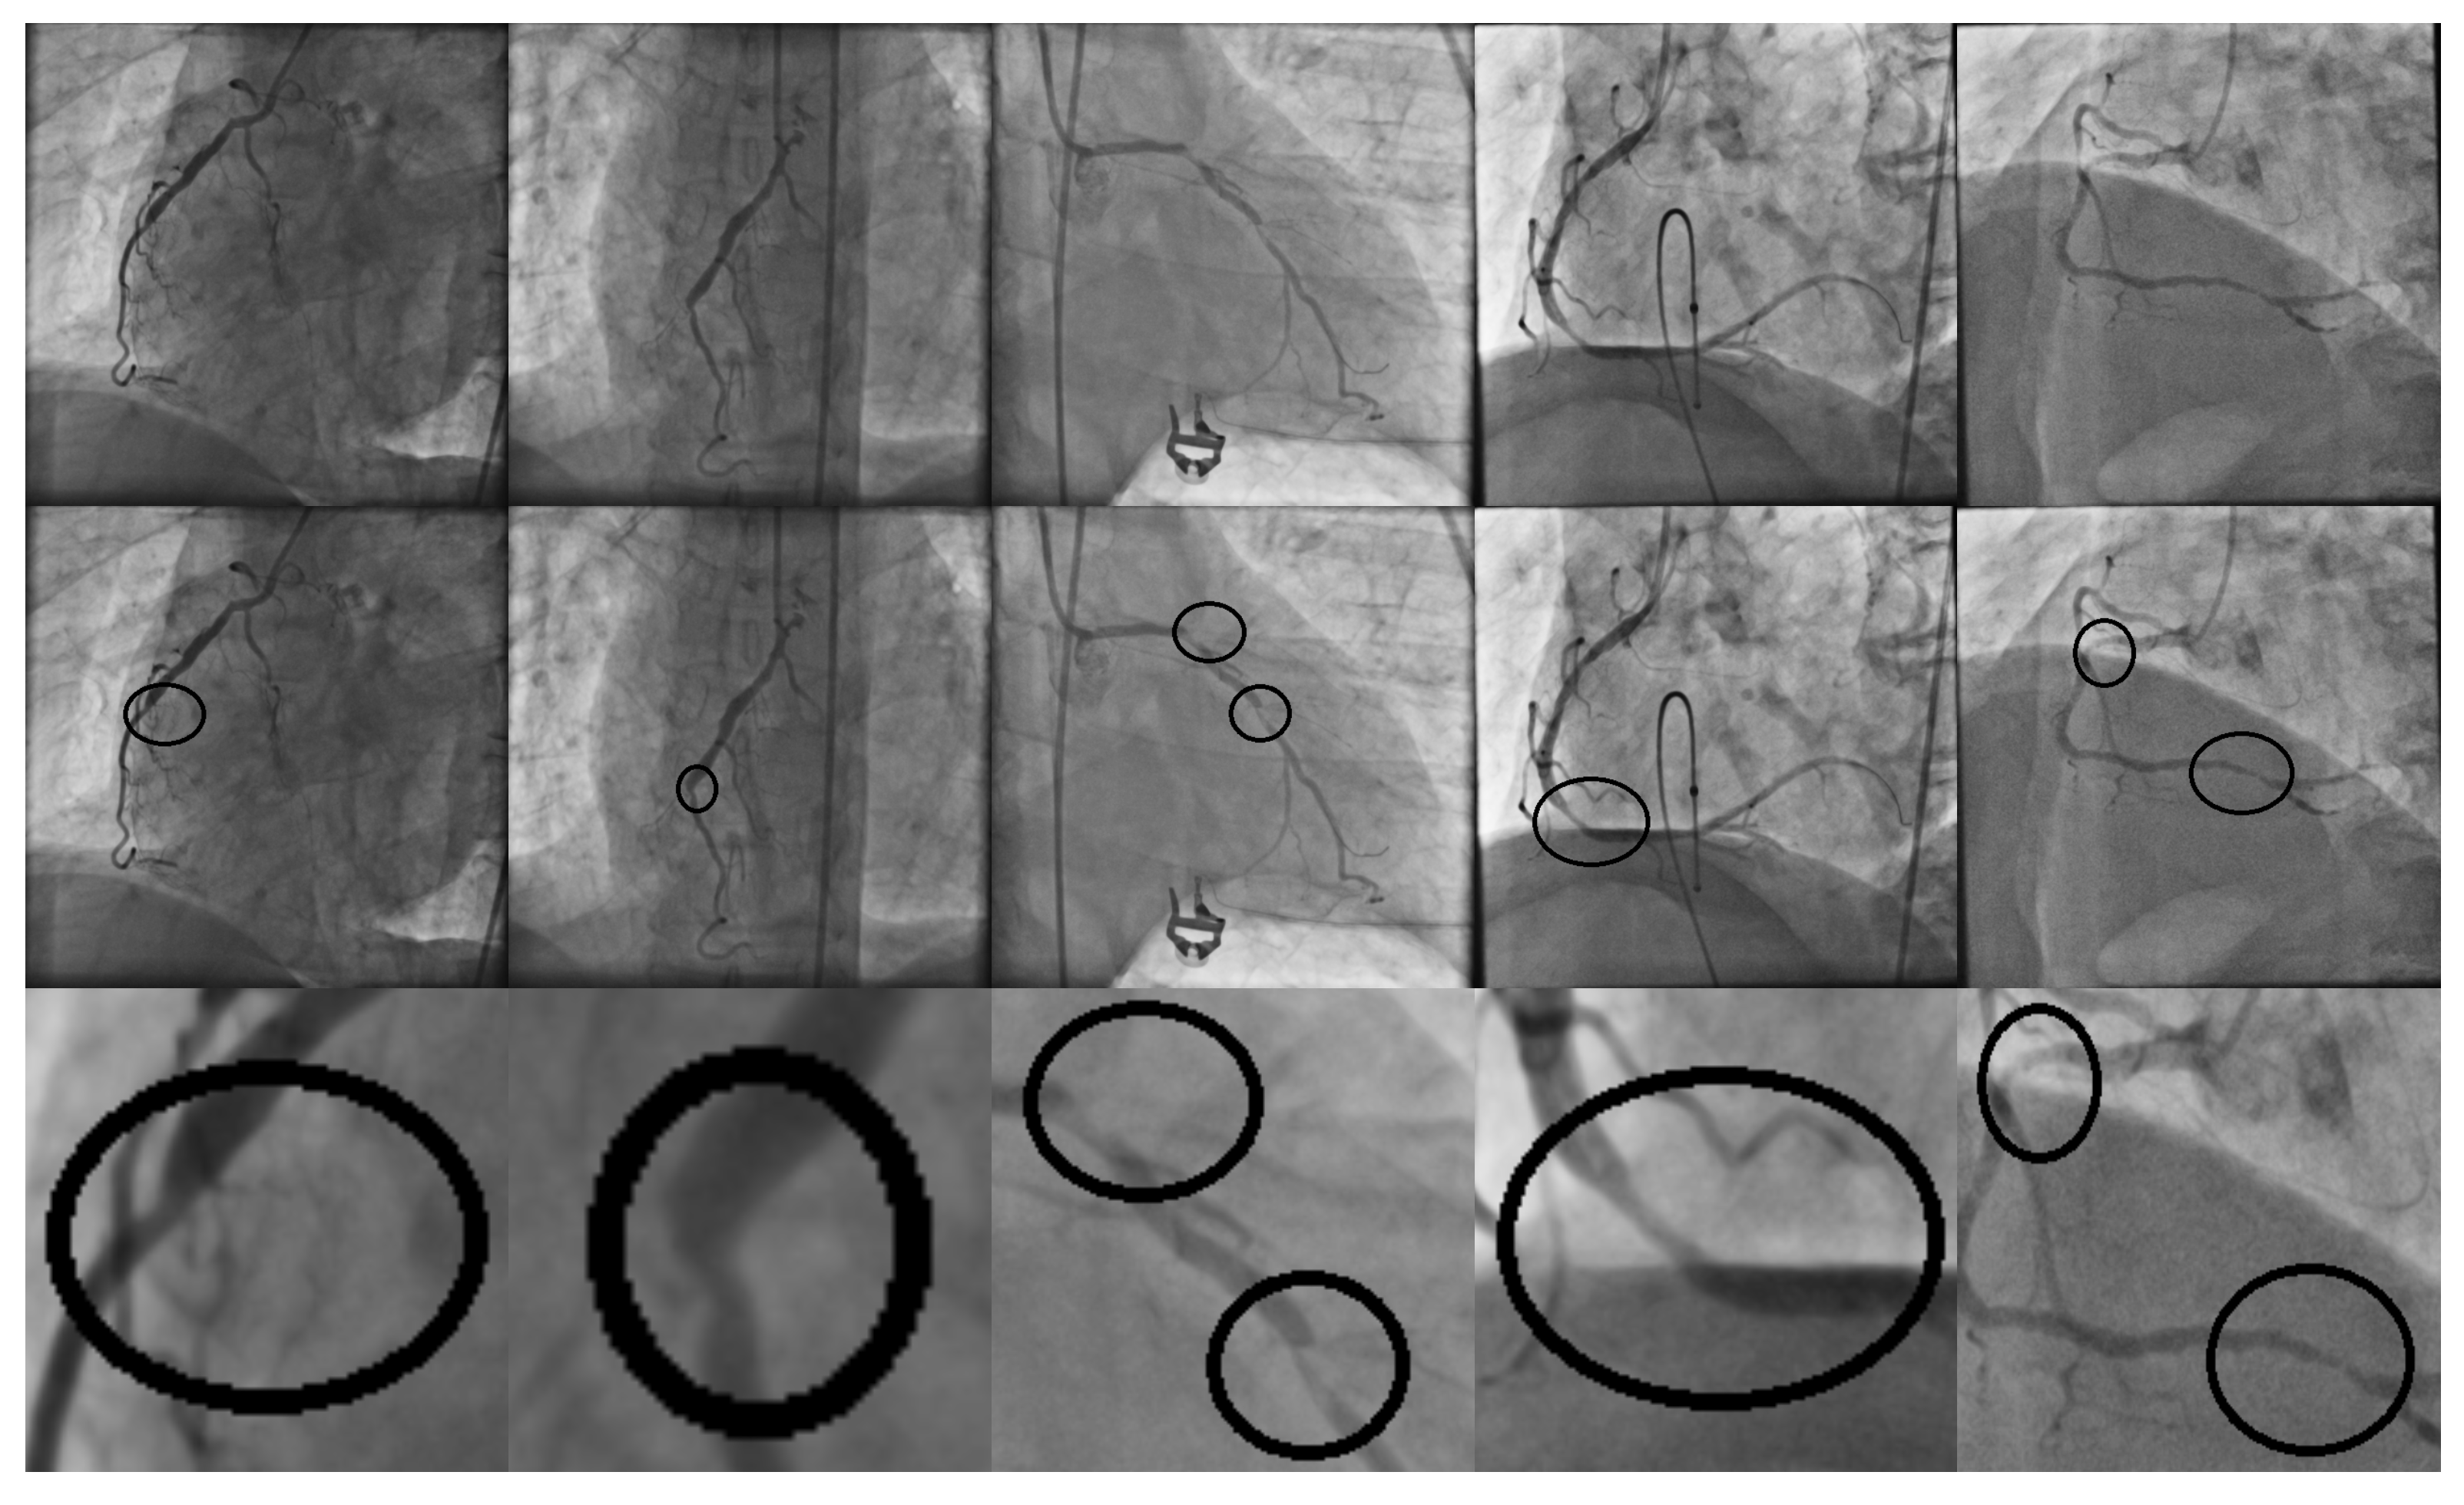

The final step of the proposed method is the classification of an independent test set using the subset of selected features. In the experiments, the first database of 608 images was divided into training (508 images) and testing (100 images) sets. Both datasets use a balance of positive and negative cases. Each patch is in a grayscale color scheme and their corresponding size is pixels. In Figure 5, a subset of sample images, along with its filter response, are presented.

Figure 5.

Patch samples from a database of 608 images. Rows (1) and (2) correspond to positive stenosis cases. Rows (3) and (4) correspond to negative stenosis cases. Column (a) corresponds to the original patch image. Columns (b–i) correspond to the different vessel enhancement method responses, as follows: Frangi, Salem, simple-scale Gabor, multi-scale Gabor, multi-scale linear, multi-scale matched filter, single-scale matched filter, and top-hat operator.